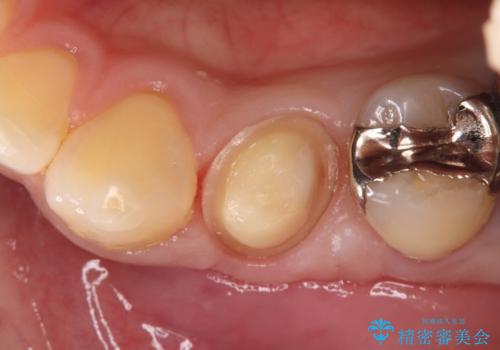

- 左下4番の奥歯に、歯肉の下まで進行した深い虫歯を認め来院されました。通常であれば神経を抜く必要があるほど深い虫歯でしたが、患者様の歯をできる限り保存するため、歯の神経を抜かずに残すことを目指す治療計画を立案。歯肉の下にある虫歯を適切に治療するため、歯周外科処置で歯肉のラインを調整した上で、精密なセラミッククラウンで修復することになりました。

まず、虫歯を徹底的に除去するために、歯周外科処置で歯肉のラインを調整し、治療部位を露出させました。その後、神経に近接した深い虫歯を慎重に除去。神経の保護処置を施し、歯の神経を抜くことなく保存することができました。型取りから、患者様の歯の色や形に合わせたオーダーメイドのセラミッククラウンを作製。最終的に、精度の高いクラウンを装着し、咬み合わせを細かく調整しました。これにより、神経を温存しながら、虫歯の再発を防ぎ、快適な咬み心地を取り戻していただけました。